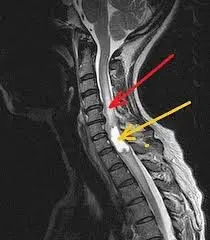

На знімку МРТ, який представлений нижче, видно не тільки нижній шийний відділ хребта, але і грудний. Вдале поєднання, так як шийно-грудне з’єднання часто є причиною больових відчуттів:

При тривалих і стійких больових проявах з боку хребта, крім МРТ шиї, іноді необхідно робити МРТ-обстеження грудного відділу.

Перевагою МРТ шийного відділу хребта є те, що можна дослідити стан спинного мозку. Це дає змогу вчасно виявити так звану мієлопатію (зміна структури спинного мозку, яка призводить до зміни функції).

Але найбільш поширеним об’єктом обстеження при проведенні мангіто-резонансної томографії шиї є шийний відділ хребта. Обстеження показує стан не тільки шийних хребців, але і дисків. Як правило, поперечний переріз хребетного каналу вимірюється на рівні протрузії дисків, що є вкрай важливою інформацією для прийняття рішення щодо лікування. Слід зазначити, що ці показники важливі при МРТ-дослідженні будь-якого відділу хребта.